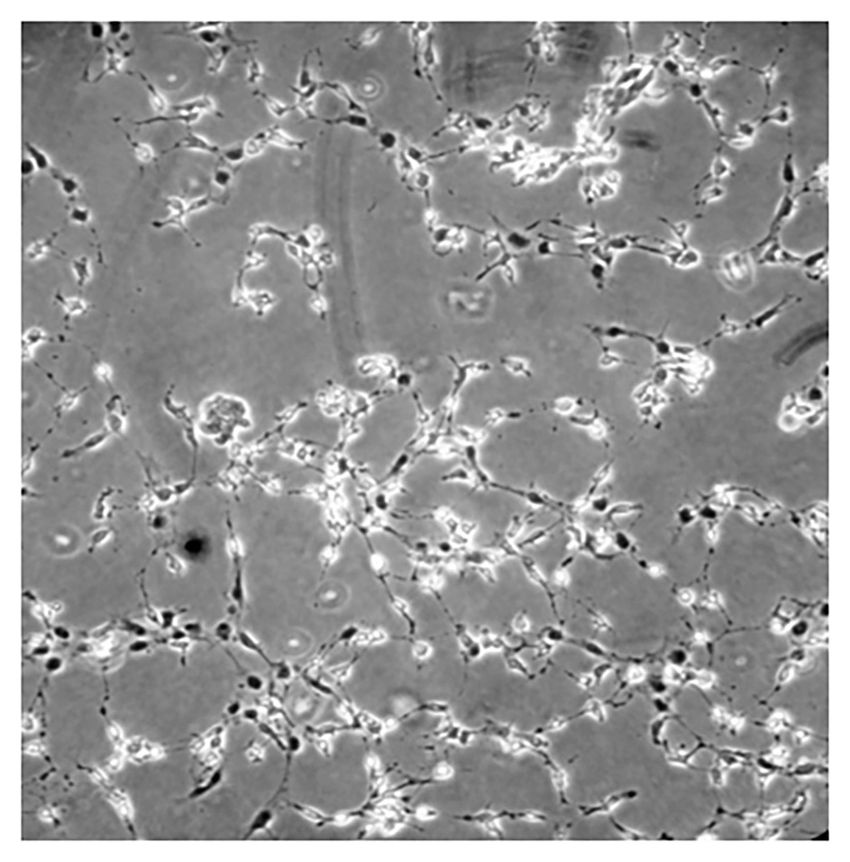

Stem cells in the dental pulp of exfoliated baby teeth exhibit fibroblast-like cell morphology when cultured in vitro.

Culturing dental pulp stem cells under neurogenic conditions induces morphological changes characterized by elongated cell bodies and neurite-like extensions, consistent with a neuron-like phenotype.